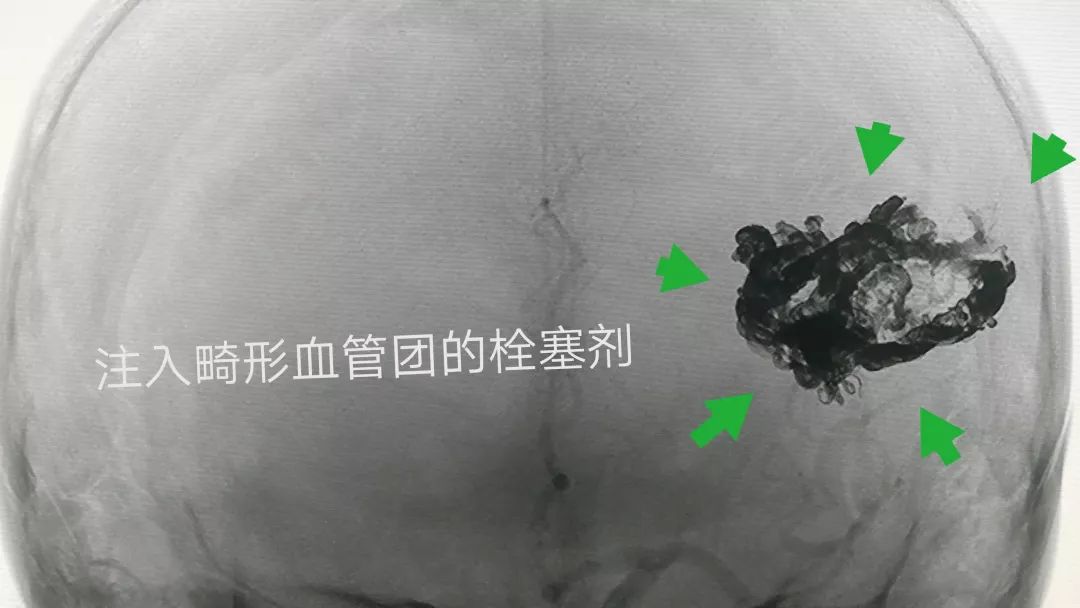

畸形团内注入的栓塞剂清晰可见(下图)

患者是2年前做的栓塞手术,当时是大部栓塞约80%,残留部分给予射波刀治疗,今天复查造影发现血管畸形完全治愈!真替他高兴!

脑血管造影复查血管畸形完全治愈,没有残留(下图)